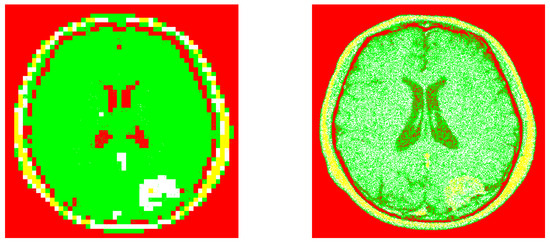

Figure 6.

The corresponding image segmentations (from the example 1). Left: Processed image by using our design. Right: Processed image by invoking the reference method.

In the previous section we have granted our recent algorithm on image segmentation based on confidence interval statistical theory. According to our numerical experiments, our method presents better performance in comparison to the standard process. For instance, from the first example, the processed image, in our case, was able to classify image segmentation more efficiently than the standard method. For the second example, it is clear that there is something around the object center almost imperceptible by the standard method. Finally, Equation (1) was invoked because according to the statistical theory, the confidence interval gives a zone where the population mean value is probably located. In our philosophy, this interval reflects the location of the hight content information versus the noise entropy.